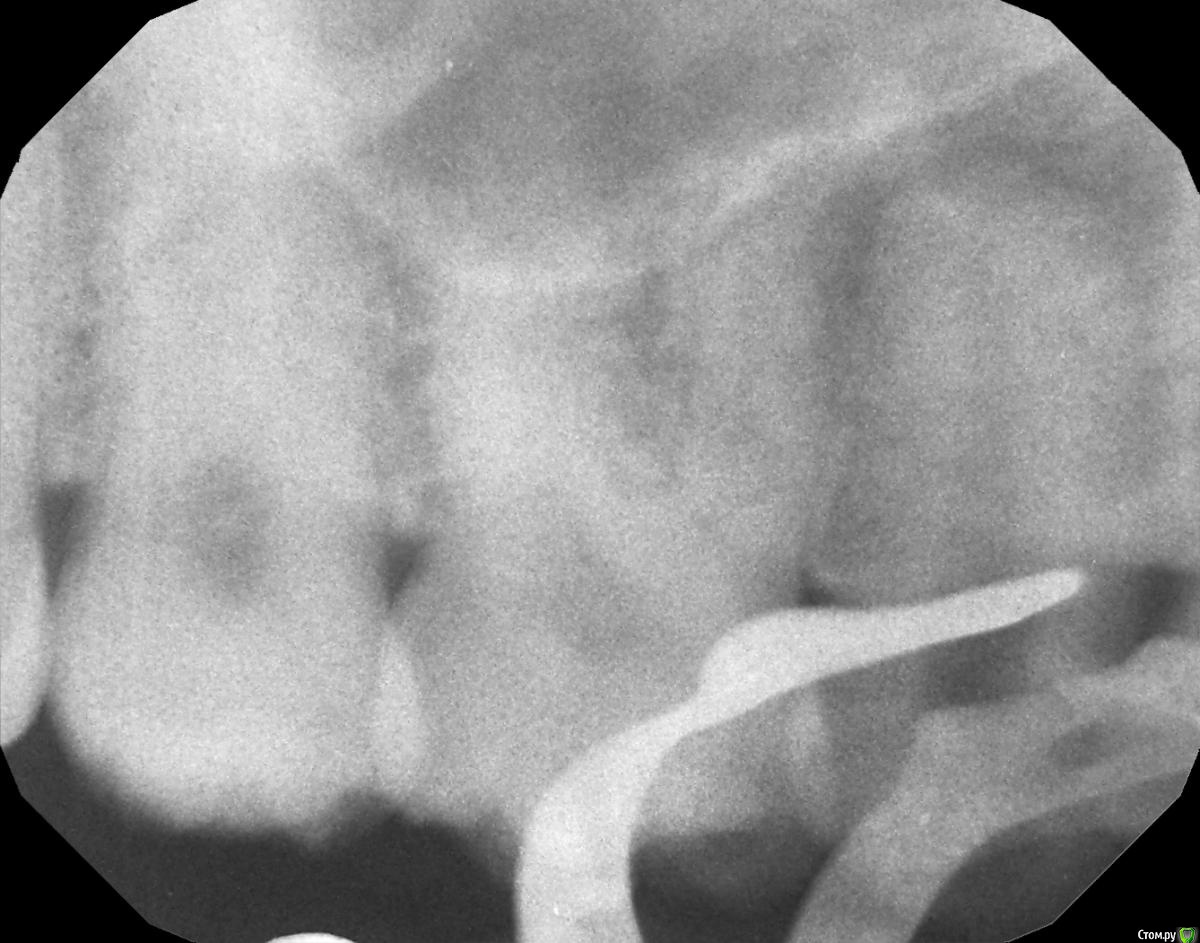

hichi Опубликовано 25 сентября, 2015 Автор Поделиться Опубликовано 25 сентября, 2015 (изменено) покажите все снимки начиная с первого Гарриевич сказал(а) 22 Сен 2015 - 00:35: покажите все снимки начиная с первого + 1 пожалуйста первичное эндо когда заболел от горячего искали доп. анатомию кальций с ложным ходом есть только один снимок, который в самом первом сообщенииесть еще один через 3 мес после лечения но он не совсем удачно сделан, думаю ничем вам не поможет Изменено 25 сентября, 2015 пользователем hichi Ссылка на комментарий